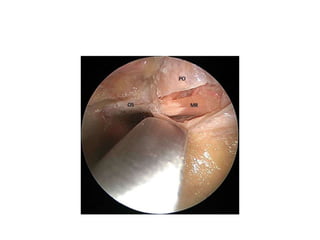

Immediately after removing the

periorbita

Frontal N. devides into Sup.Troch.N.

& Supraorb.N. – NOTE Fal.Lig

Parts of SOF

1. Lateral part- LFT [ Liver functional tests ] Menumonic – Lacrimal N., Frontal

N.,Trochlear N.

2.Middle part

3. Medial/Inferior part